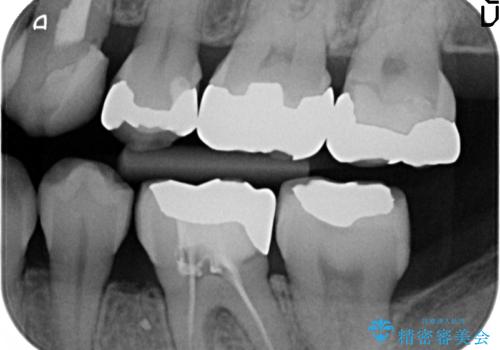

- 左上犬歯の一部が歯ぐきの中まで虫歯になっており、部分矯正をして歯を引っ張り出しました。(エクストリュージョン)

左:虫歯を除去したところ。遠心が歯ぐきより深い状態です。中:そのままかぶせようとすると、遠心が歯ぐきが腫れやすい状態です。右:エクストリュージョンをしたことで、遠心の歯ぐきの腫れが収まっていることがわかります。

エクストリュージョンをしたことで、いくら歯磨きを頑張ってもどうしても腫れてしまう歯肉に対して、歯周囲組織の位置関係を変えることで根本的に解決しました。

歯の変色もあるため、最終的にはクラウンとしました。